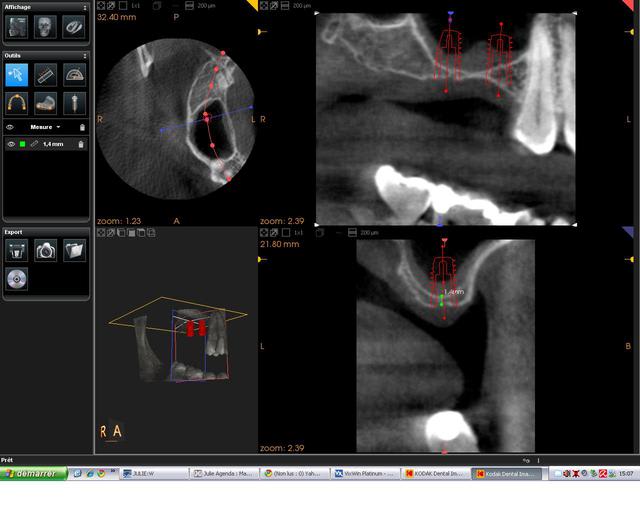

bonsoir

je voulais partager avec vous ce cas de soulevé sinusien par voie latérale avec implantation immédiate qui est possible malgré la faible quantité osseuse résiduelle comme on peut s'en rendre compte sur la 3D grâce aux caractéristiques de l'implant.

on peut noter sur la dernière pano qui est réalisée à 2 mois post op la densification du matériau qui peut s'expliquer de différentes manières:

- la petite fenêtre réalisée (technique DASK)

- le matériau OSTEON qui est un biphasé dont chaque particule d'HA est enrobée de béta TCP ce qui rend son intégration plus rapide